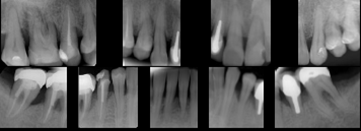

Onemocnění parodontu patří ke druhému nejčastějšímu onemocnění v dutině ústní, ihned po zubním kazu. Nejčastějším problémem je gingivitis- zánět dásní a také parodontitis - zánětlivé onemocnění postihující závěsný aparát zubů, přilehlou dáseň i kost. Mezi časné projevy gingivitidy patří krvácení dásní, které může v případě parodontitidy přejít ve tvorbu parodontálních chobotů, spojené se zápachem z úst, tvorbou hnisu, bolestmi a viklavostí zubů v důsledku ztráty kosti. Tomuto onemocnění se dá úspěšně předcházet pravidelnými kontrolami, sanací chrupu a péčí v rámci dentální hygieny.

Periometr - první plně automatizovaný přístroj pro zjištění periodontálního statusu pacienta - diagnózy, léčby a profylaxe parodontitidy a dalších onemocnění. Díky správnému určení periodontálnímu statusu pacienta lze včas odhalit a minimalizovat objevující se obtíže.